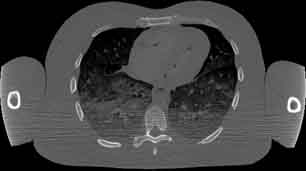

CT